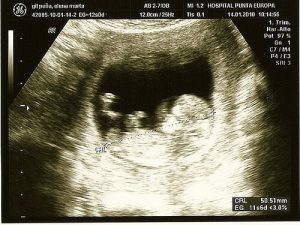

Ultraljud:

Det är en väldigt vanlig procedur som är användbar både för att upptäcka problem och för att få den första bilden av ditt barn.

Ultraljudet ger paret chansen att få reda på barnets kön, och gör det lättare att upptäcka anomalier som hjärtdefekter och kromosomförändringar.

Extra detaljerade ultraljud rekommenderas för att observera möjliga defekter som fostret kanske uppvisar. Det föreslås om fosterdiagnostiken visar på möjliga anomalier.

Det är en icke-invasiv teknik där en apparat skapar en bild med hjälp av vågor. Vågorna skadar inte barnet, och gör att man kan se inuti livmodern.